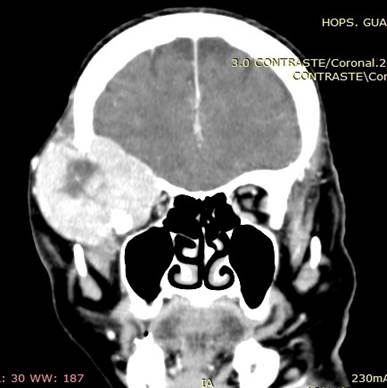

Ilustración 10 Metástasis cerebral con destrucción del occipital.

Fuente: Hospital de Especialidades Guayaquil “Doctor Abel Gilbert Pontón”.

Autor: Dr. Fernando Moncayo A.

Paciente de 68 años de edad, que ingresa referida de otra institución por presentar más tumoral en región occipital derecha de gran tamaño dura muy adherida, dolorosa con circulación colateral; paciente desorientada en tiempo y espacio, irritable y poco colaborativa, en algunas ocasiones ha presentado convulsiones tónico clónicas. Además, presenta masa cervical voluminosa, a nivel tiroidea, dura, adherida a estructura aéreas y vasculares.

Se toma biopsia con aguja gruesa de lesión tumoral cervical y tumoración occipital encontrando carcinoma papilar variante oncocitica.  Paciente fue tratada por el departamento de oncología clínica en forma paliativa y con Sorafenib por no haber mejoría con radio-yodo.